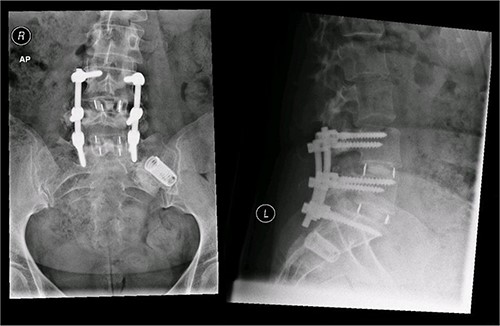

A magnetic resonance imaging (MRI) scan performed in October 2013 (Fig. 1) identified non-compressive, degenerated discs at L4/5 and L5/S1 vertebral levels. However, clinically as the patient was more tender over the left SI joint and the pubic symphysis (Fig. 2), a left sacroiliac joint fusion and symphysis pubis plating procedure was performed in August 2014 (Fig. 3). Following a short period of relief, the pain returned. Subsequently, the patient underwent a 360° fusion (front and back) of the L4/L5 and L5/S1 discs in August 2015 (Fig. 4), a year following the previous surgery. Once again, following a brief period of relief, the symptoms returned. The assumption then was that the initial fusion of the left sacroiliac joint had failed. Therefore, a revision fusion of the left sacroiliac joint and a primary fusion of the right sacroiliac joint was undertaken in August 2017 (Fig. 5).

Postoperative X-ray of the pelvis following the second fusion surgery: postoperative X-ray of the pelvis, performed in January 2016 following the second fusion surgery, showing 360° (front and back) fusion of the L4/5 and L5/S1 disc space.